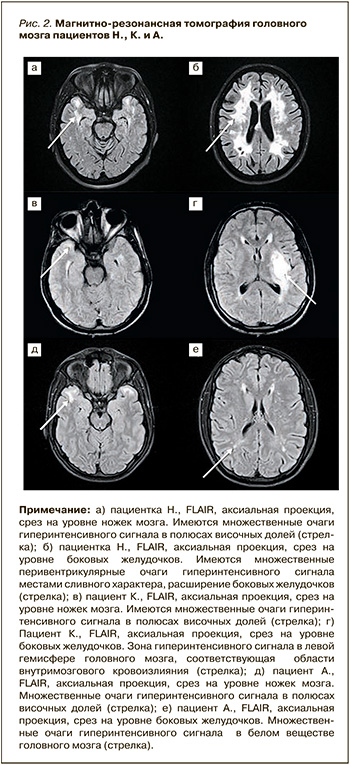

Таким образом, клиническими особенностями заболевания у Н. являлись: манифестация заболевания с легких, периодически нараставших и затем регрессировавших координаторных и двигательных нарушений; отсутствие цефалгического синдрома на всех этапах болезни; развитие лакунарного инсульта с легким и быстро регрессировавшим неврологическим дефицитом через 11 лет после начала заболевания; медленное нарастание когнитивных нарушений, не достигших степени деменции к 49-летнему возрасту. Нейровизуализационные изменения головного мозга (рис. 2а, 2б) имели сходство с таковыми при рассеянном склерозе (за исключением изменений в передних отделах височных долей), что во многом способствовало ошибочной диагностике последнего вплоть до момента развития у пациентки инсульта.

На МРТ головного мозга (29.05.2022) определялись кистозно-глиозные изменения в области базальных ядер слева, а также множественные сливные гиперинтенсивные очаги в белом веществе лобных, теменных, полюсах височных долей (см. рис. 2в, 2г). Таким образом, у пациента К. синдром ЦАДАСИЛ дебютировал геморрагическим инсультом с грубым неврологическим дефицитом. Обращало на себя внимание отсутствие головной боли до манифестации инсульта, а также отсутствие когнитивных нарушений на фоне выраженных нейровизуализационных изменений головного мозга.

Применение соответствующих шкал указало на наличие астенического синдрома при отсутствии признаков депрессии (см. табл.). Учитывая отягощенный наследственный анамнез, пациенту было предложено провести МРТ головного мозга. На МРТ (10.03.2023) в белом веществе лобных, теменных и передних отделах височных долей юкстакортикально, субкортикально и перивентрикулярно были обнаружены множественные гиперинтенсивные сигналы на Т2-ВИ и FLAIR размерами 0,2–1,8 см (рис. 2д, 2е). Поскольку имелись указания на эпизоды галлюцинаций, был также проведен шестичасовой мониторинг электроэнцефалограммы (ЭЭГ-мониторинг), который эпилептиформной активности не выявил.

Другая общая особенность всех описанных пациентов – наличие характерных для ЦАДАСИЛ изменений на МРТ головного мозга в виде симметричных зон гиперинтенсивного на Т2-ВИ сигнала в перивентрикулярном белом веществе и передних отделах височных долей.